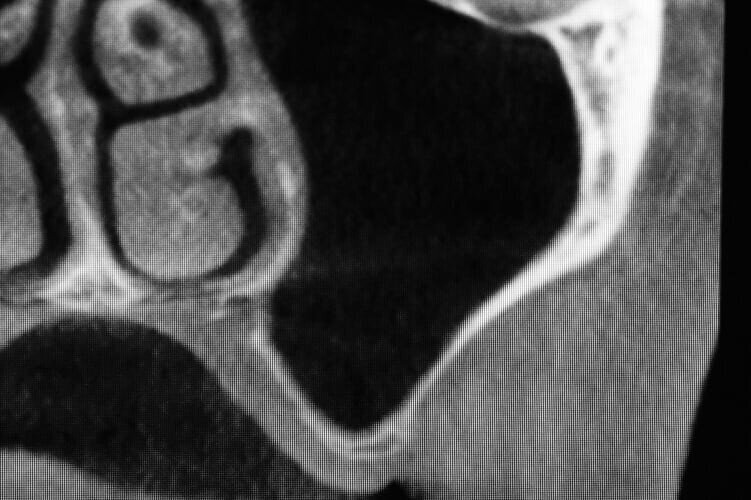

In questo case report è stata selezionata una paziente di sesso femminile, S.P. (54), non fumatrice, con buona igiene orale e con anamnesi negativa all’assunzione di farmaci, ad allergie, disturbi metabolici e patologie sistemiche (Figg. 1-3). È stata proposta una tecnica di rialzo del seno mascellare eseguita mediante strumenti piezoelettrici (Piezosurgery®, Mectron, Genova, Italy) (Figg. 9, 10, 13).

In seguito all’intervento di rialzo di seno mascellare con contestuale GBR è stata eseguita la radiografia ortopanoramica che mostra il corretto riempimento dell’area atrofica del seno mascellare con granuli cortico-spongiosi di osso di origine bovina. Al controllo dopo tre settimane i tessuti molli dell’area trattata risultano perfettamente guariti. La TC Dentalscan effettuata dopo 6 mesi per il controllo della zona rigenerata evidenzia la perfetta guarigione della zona con aumento dello spessore osseo di 5 mm e dell’altezza ossea di 11 mm.